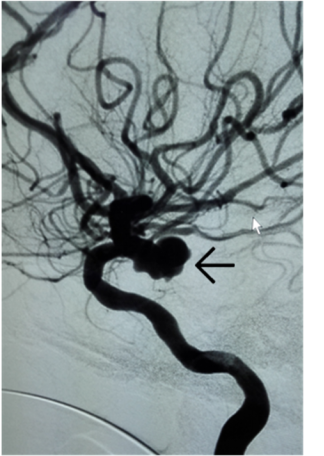

女性,63岁,蛛网膜下腔出血,后交通动脉瘤破裂出血,动脉瘤大,易再出血,死亡率达60%以上。行血管内动脉瘤栓塞术,手术安全、创伤小、效果好,避免再出血风险。

手术前,后交通动脉瘤(箭头处)